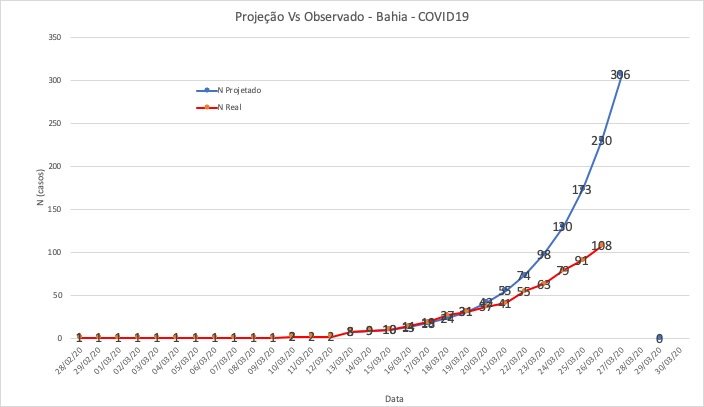

Gráfico aponta que casos de coronavírus na Bahia estão 46% abaixo do projetado

O secretário de saúde da Bahia, Fábio Vilas-Boas, voltou a apresentar na manhã desta sexta-feira (27) a comparação entre casos confirmados e projetados de coronavírus na Bahia. Em um gráfico, o gestor da pasta indicou que o número de infectados está 46% abaixo do esperado.

“Terminamos a quinta-feira (26) com 108 casos #COVID?19 em toda a Bahia. A inclinação da curva continua menos acentuada que a previsão original. O aumento médio diário tem se mantido em 23%. À medida em que bairros mais populosos forem atingidos, espera-se um incremento maior”, indicou.

Ainda segundo o gráfico, são 306 casos projetados para esta sexta-feira (27). Como tem sido padrão nos últimos dias, a Sesab deve divulgar novos boletins para atualizar os casos da doença.